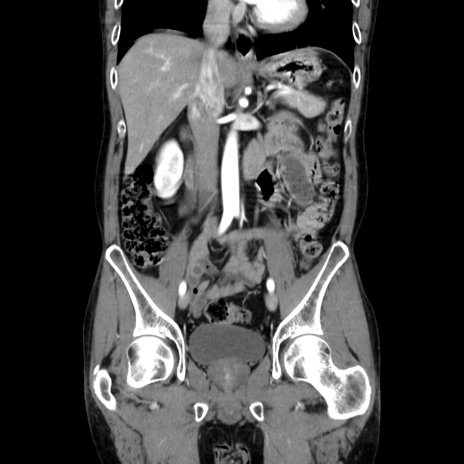

症例37(冠状断像)

【症例】40歳代 男性

【主訴】腹痛

【現病歴】4時間ほど前に電車に乗車中に臍部上より腹痛出現。徐々に増悪し起立困難となり、救急外来受診。生ものは数日食べていない。今朝お雑煮を食べた。

【身体所見】BT 36.8℃、BP 117/84mmHg、HR 91/min、SpO2 97%、苦悶様、腹部:臍上部広範囲圧痛あり、反跳痛±

【データ】WBC 8100、CRP 0.03